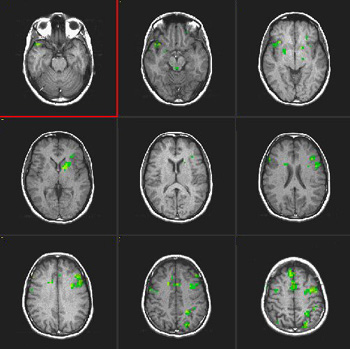

Estudios en hablantes bilingües tardíos

| Sujeto |

Mujer diestra de 34 años de edad Lengua materna: Español

| Paradigma |

Tipo: Tarea de fluidez verbal

ACTIVADO: Recordar verbos relacionados con los sustantivos presentados

DESACTIVADO Deletrear las palabras proporcionadas |

| Estadísticas |

| Método estadístico |

Valor P |

Puntuación Z |

| Prueba T |

0,0001 |

3,8 |

| Imágenes |

Español

|

Inglés

(Hacer clic en las imágenes para agrandarlas)

| Activación |

Se observa una activación en el área de Broca en ambos idiomas. La activación talámica derecha se observa solo en el segundo idioma. Se observa también una mayor activación de la circunvolución frontal inferior derecha en el segundo idioma que en la lengua materna. El área motora suplementaria es más pronunciada en la derecha en ambos idiomas. |